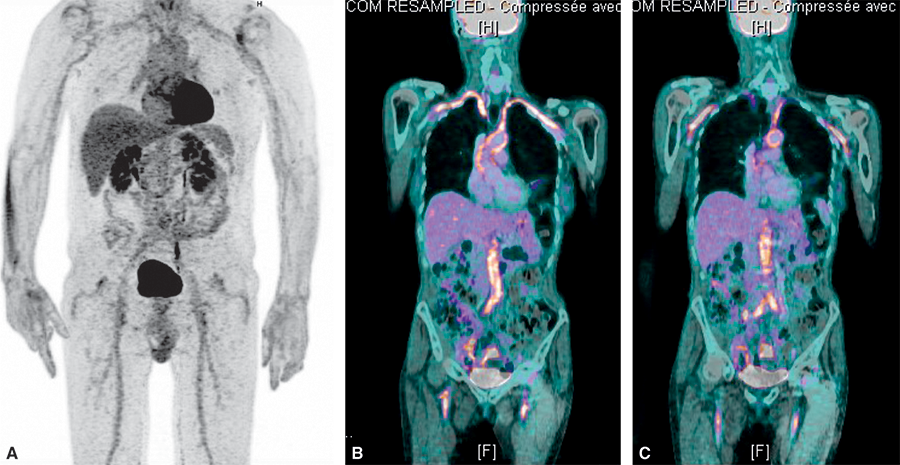

Fig. 16.7.

TEP-scanner dans l’artérite à cellules géantes.

Hyperfixations très évocatrices d’une artérite au niveau des artères axillaires (flèches blanches), de l’aorte abdominale (flèches rouges) et des artères fémorales (flèches jaunes).

Cet examen au 18FDG, comme dans la PPR, permet de visualiser les atteintes des vais- seaux extracrâniens (fig. 16.7) et d’obtenir une cartographie de l’ensemble des vaisseaux atteints, montrant des zones inflammatoires de fixation intense du traceur radioactif utili- sé. C’est actuellement un des examens de référence dans le diagnostic de l’artérite à cel- lules géantes extracrâniale. Les évolutions techniques rapides de la TEP permettent maintenant d’étudier également les vaisseaux crâniens sur les appareils les plus modernes.

Les coupes scanographiques associées permettent de visualiser plus précisément l’atteinte de l’aorte. Son utilisation pourrait permettre d’évaluer l’activité de la maladie et constituerait un outil intéressant pour le suivi. Il n’est cependant pas réalisé de manière systématique.